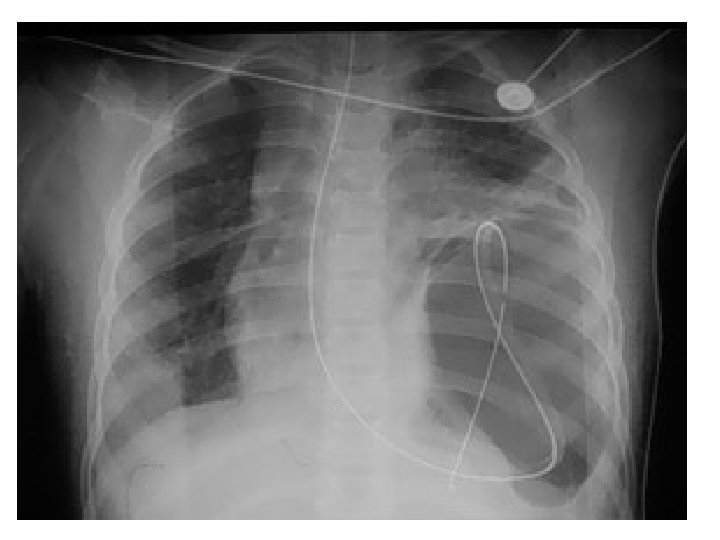

H. MEDİASTENİ GEÇEN YARALANMA • Penetran objeler major mediastinal yapılara (kalp, ana damarlar, …) zarar verebilir. • Cerrahi konsültasyon zorunludur. • Hemodinamisi bozuksa torasik hemoraji? , TP? , perikardial tamponad? • Hemopnömotoraksı kaldırmak ve kan kaybını takip için Bilat tüp torakostomi • Acil torakotomi endikasyonları = Masif hemotoraks

• Mediastinal amfizemi varsa özefagial ve trakeabronşial yaralanma? • Mediastinal hematom yada plevral kep büyük damar yaralanması • Nonoperatif değerlendirme planlanıyorsa acil anjiografi veya helikal CT • Anjiogram negatifse suda çözünür kontrast özefagografi • Trakeabronşial ağacın değerlendirilmesi için bronkoskopi • Kalp ve perikard USG ve BT • Mortalite hızı %20